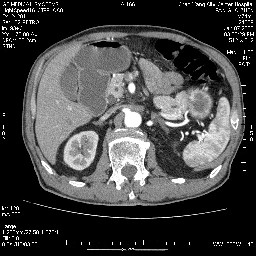

女,74岁,呕吐10余日

十二指肠水平段腔内占位伴梗阻,中等度较为均匀的强化,洗脱慢,区域淋巴结显示增多,符合腺癌表现。下腔静脉变异。

十二指肠降段扩张,水平段狭窄成鼠尾状,肠壁明显增厚,胰腺勾突增大成不均匀强化,其内可见低密度区,胆囊增大,1十二指肠水平段腺癌侵犯胰腺勾突可能大,2胰腺癌侵犯十二指肠(只有胆囊增大没有肝内外胆管扩张不好解释)代除外.

十二指肠降段扩张,水平段狭窄成鼠尾状,肠壁明显增厚,胰腺勾突增大成不均匀强化,其内可见低密度区,胆囊增大,1十二指肠水平段腺癌侵犯胰腺勾突可能大,2胰腺癌侵犯十二指肠 。

今日手术结果:胰腺钩突癌侵犯十二直肠,腹腔淋巴结转移.